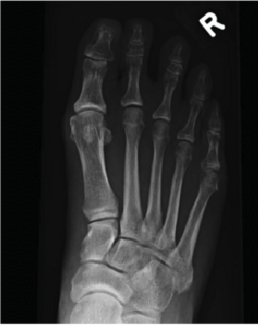

The author presents a case report on a non-diabetic male with osteomyelitis after an arthrodesis procedure. With an absorbable antibiotic cement spacer, surgeons salvaged the first ray, which is crucial in preventing subsequent foot and ankle...